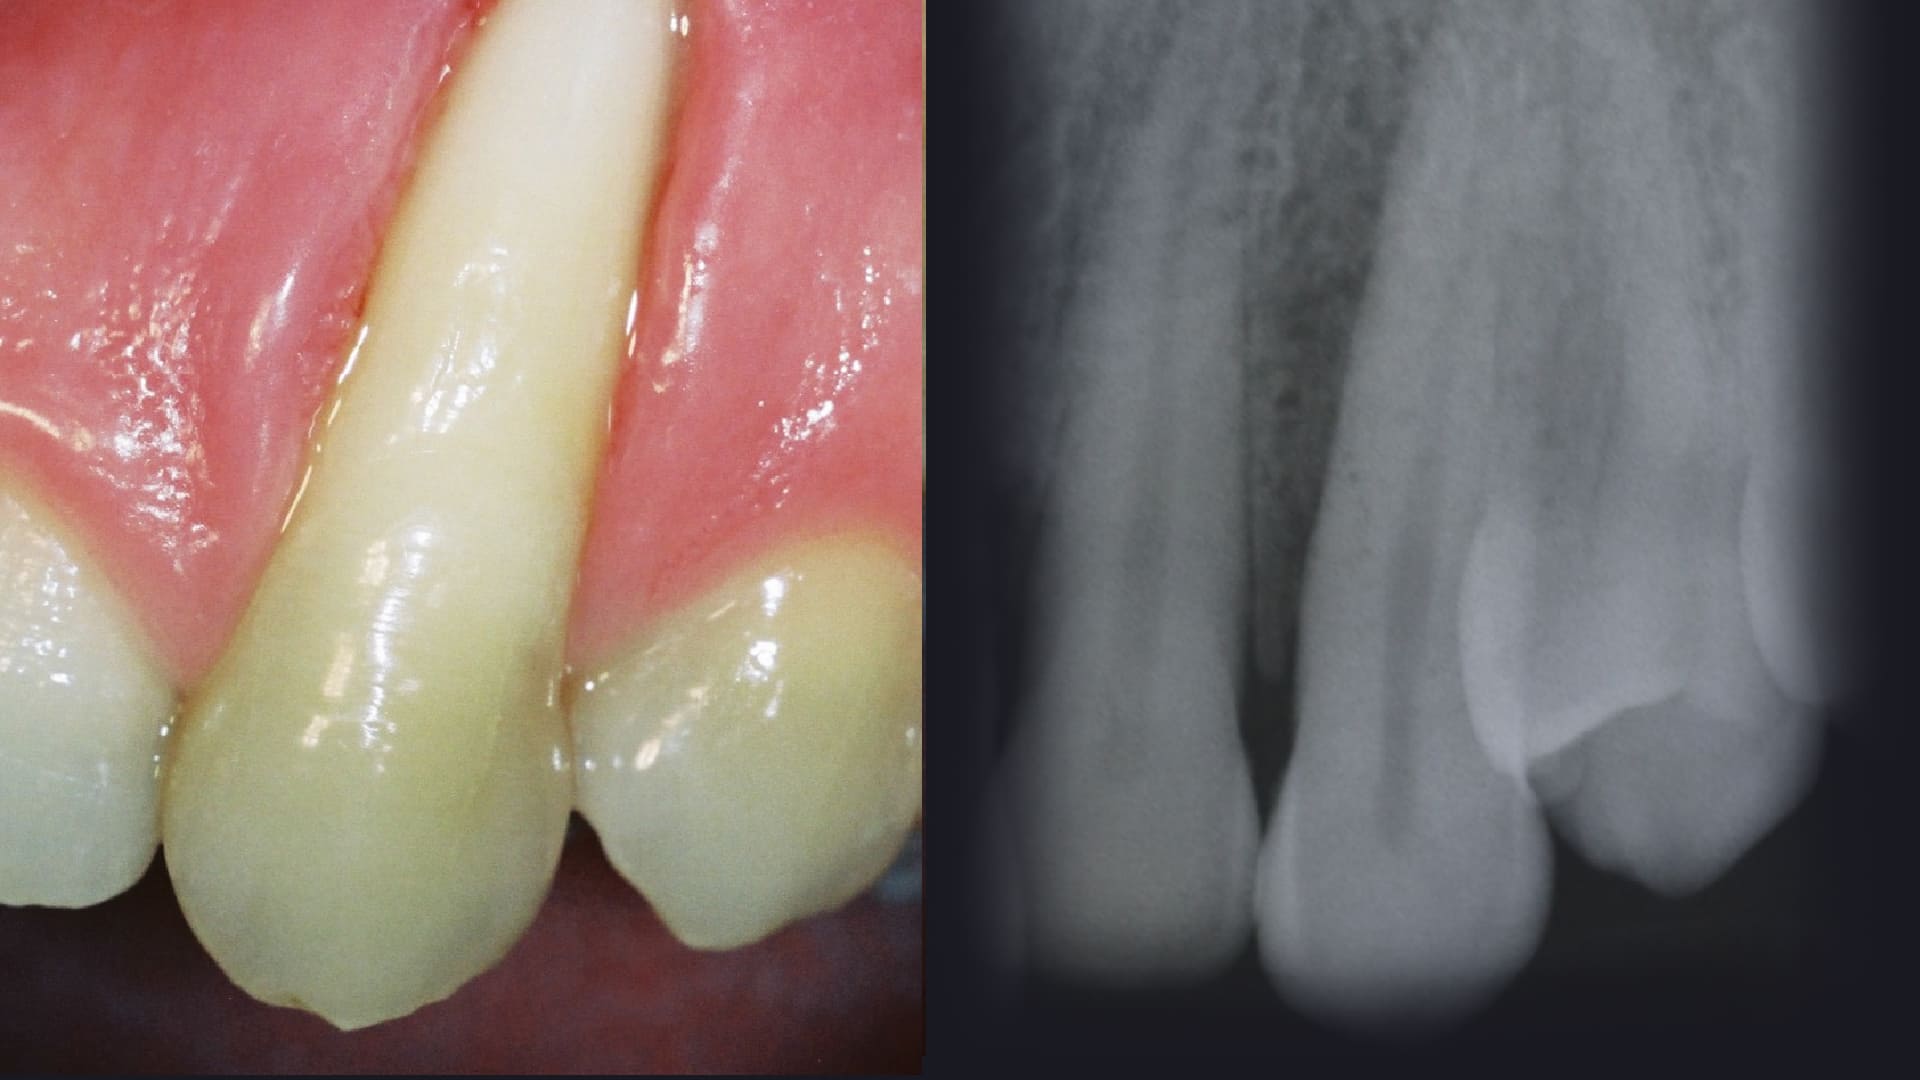

Root Coverage procedures.

CLINICAL CASES